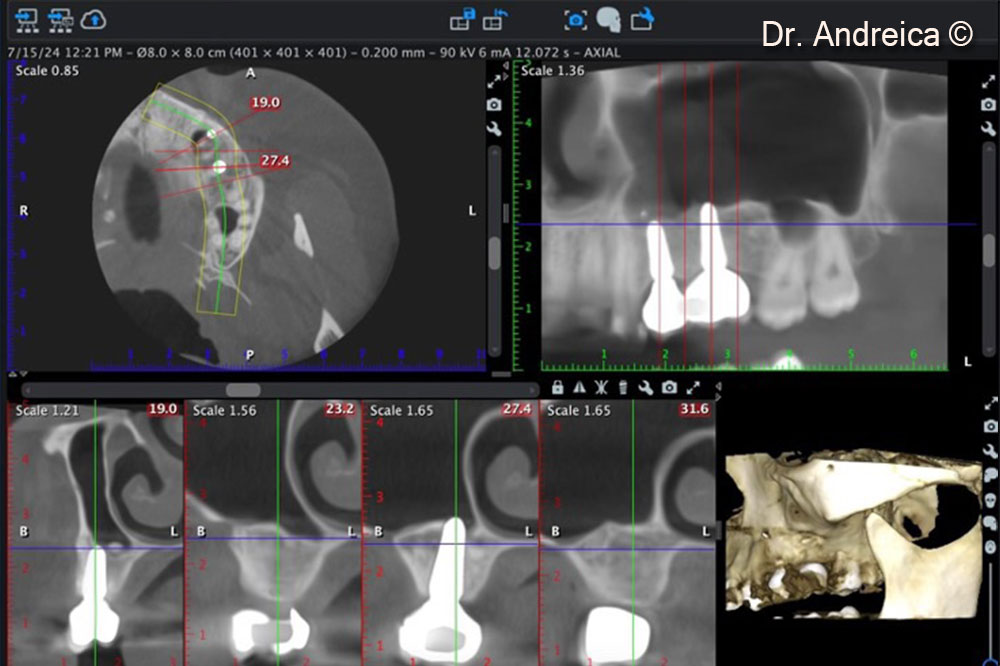

CBCT scan after 5 years showing the shrinkage of the sinus graft down to the apex of the implants and  corticalization indicating an optimal bone behaviour